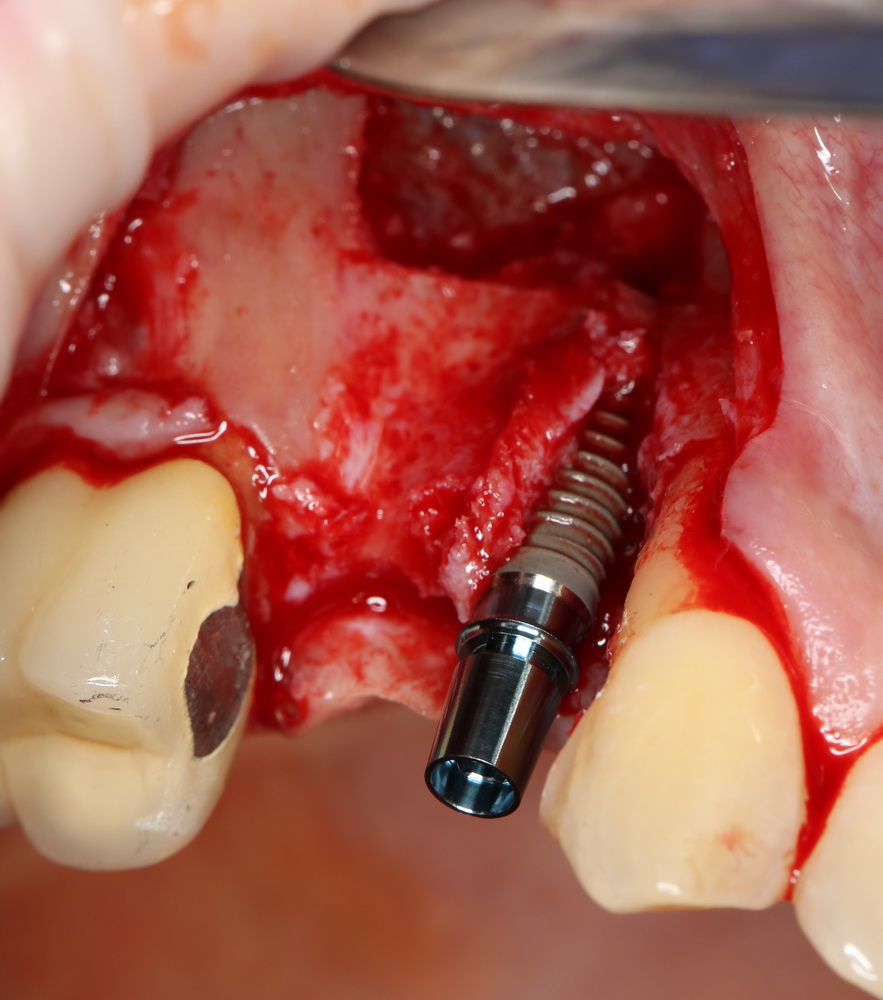

Затем устанавливаем имплантат. В данном случае, Friadent XiVE. Диаметром 3,4 мм — это минимальный размер импланта, который можно использовать в эстетически значимой зоне:

Не обращаем внимания ни на стабильность импланта, ни на объемы окружающей костной ткани. Имплантат после установки может крутиться, шататься и вращаться — правило, когда первичная стабильность была главным условием успешной имплантации, применимо лишь ко второму этапу развития имплантологии. Более того, друзья, есть импланты, которые вообще не предполагают первичной стабильности. Например, Bicon.

Очень хочется использовать имплантат поменьше диаметром (3.0 мм), но, как я уже отметил, минимальный размер в эстетически значимой зоне — 3,4 мм. Связано это с тем, что на импланты диаметром 3.0 мм выпускается очень небольшое количество супраструктур (абатментов), поэтому в дальнейшем можно столкнуться со сложностями при протезировании.